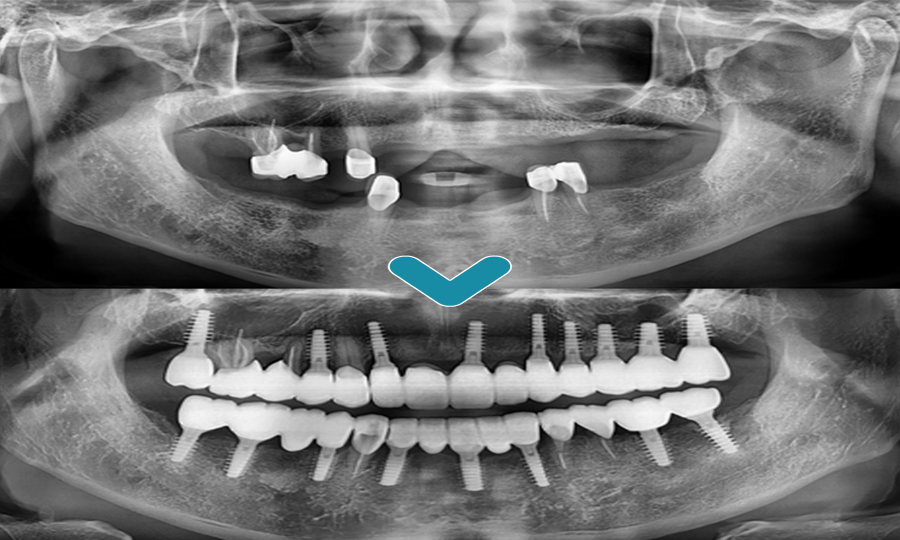

위 환자분은 본원에서 2011년도에 틀니 치료를 받으시고 잘 사용 중이셨습니다. 환자분께서 현재 사용하고 계신 틀니는 잘 맞으며 음식도 너무 잘 드시고 계시는데, 틀니는 아무래도 치아보다 약해 자주 깨지기도 하며 넣고 빼고 하는 부분이 불편해서 임플란트 식립을 생각하고 오셨다고 하셨습니다. 환자분의 엑스레이 사진을 보시면 위아래로 치아는 몇 개 남지 않은 상태입니다. 환자분께서 현재 사용하고 계신 틀니는 이 남아있는 치아에 걸어 사용하는 형태인 부분틀니입니다.

먼저 전주신시가지치과 프라임치과는 환자분의 환자분의 상태를 면밀히 파악하기 위해 3D CT 촬영을 진행하였습니다. 촬영을 통해 환자분의 잇몸 상태는 임플란트 식립을 하기에 충분함을 확인한 후, 필요한 부위에 최소침습 임플란트 식립을 진행하기로 치료 계획을 세웠습니다.

부분틀니를 걸며 힘이 많이 가해져 손상을 입은 치아는 자연치아를 최대한 살려 근관치료와 치관확장술을 진행하였으며, 치아가 없는 부위에는 위쪽 9개, 아래쪽 8개의 임플란트 식립으로 전체적으로 이상적인 교합을 맞추어 치료를 마무리하였습니다.

치료 전후의 모습입니다.